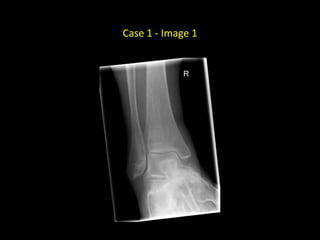

Case 1

• 30 year old with pain in the right ankle after a fall

Case 1 - Image 1

Case 1 - Image 2

• AP and lateral radiographs of

the right ankle in a skeletally

mature patient

• There is an oblique, non-

displaced fracture of the

distal shaft of the right tibia